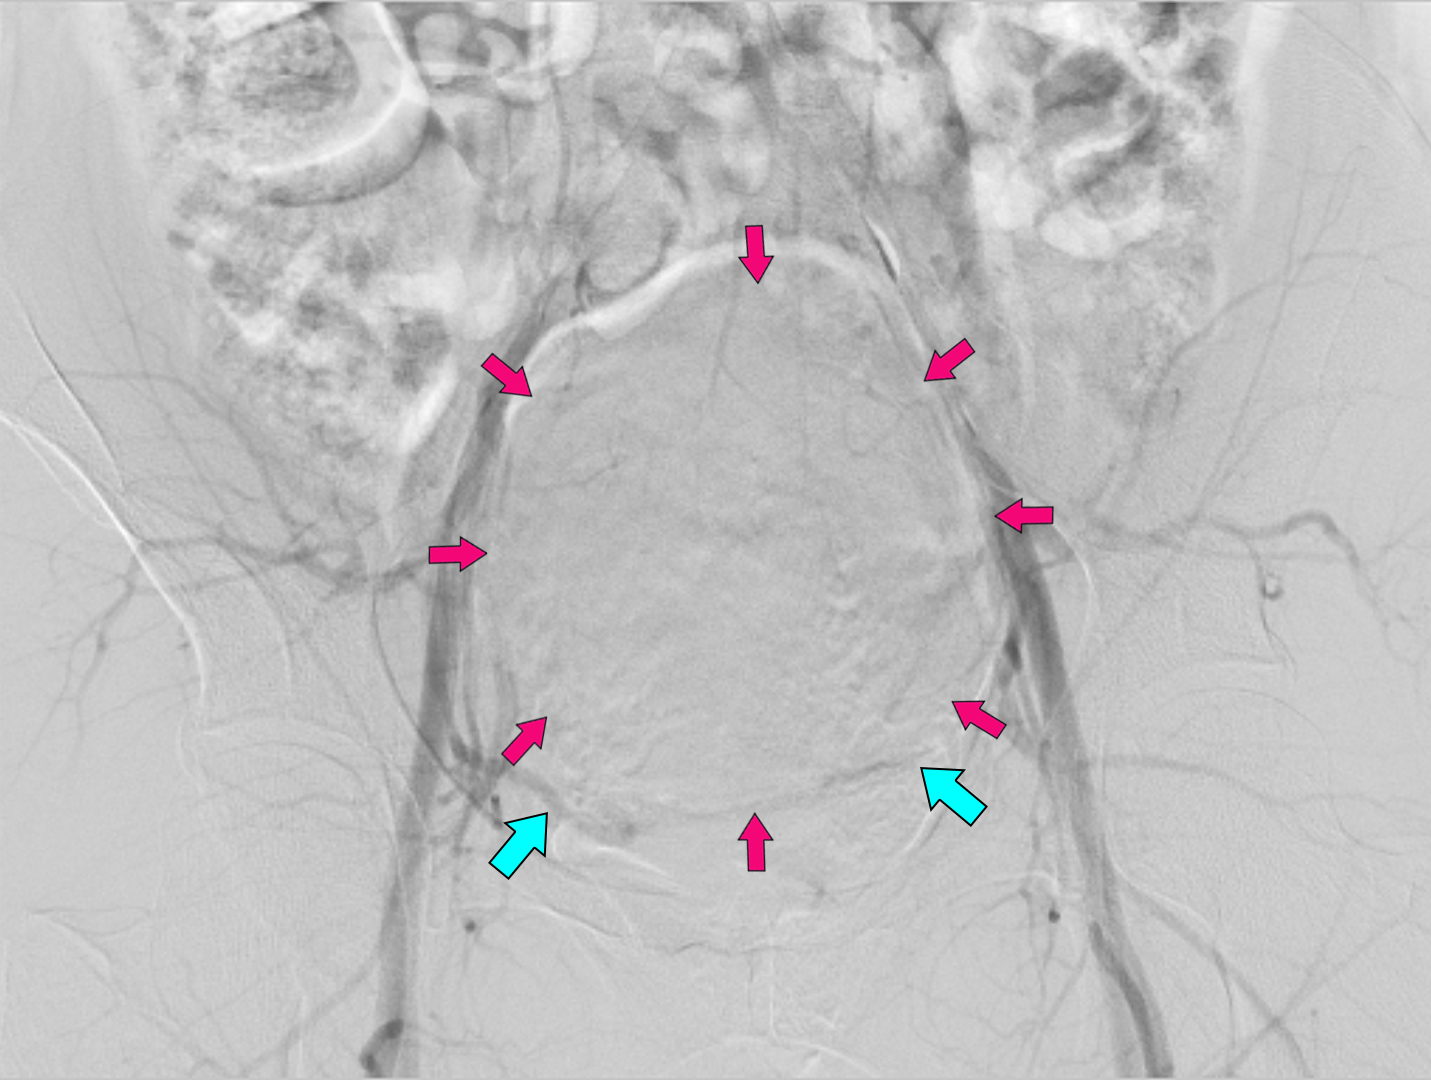

До/Після виконання втручання

Блакитними стрілочками позначено праву та ліву маткові артерії

Контрольний знімок з черевної аорти. Візуалізуються магістральні частини маткових артерій, кровотік в фіброміомі повністю припинений. Результат емболізації добрий. Процедуру завершено